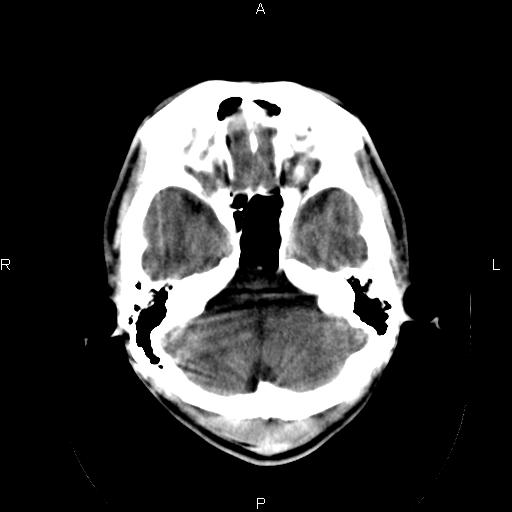

男性,40岁,反复头痛,视物旋转一月余,无呕吐,pe未见明确异常。

我的问题是上矢状窦高密度怎么解释?请各位专家不吝指教,谢谢!